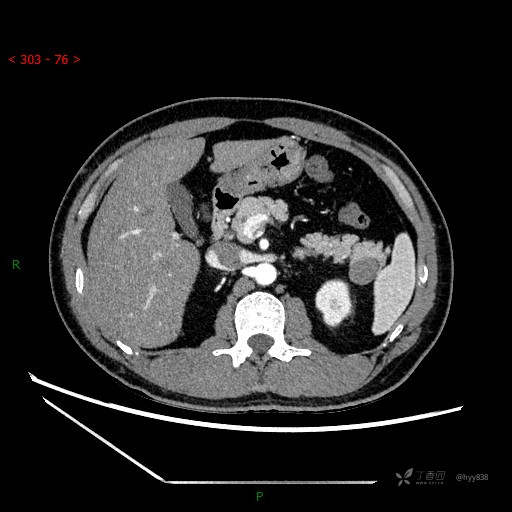

增强静脉期

CT值

42hu 48hu 57hu